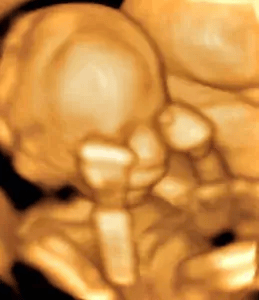

a baby human in the womb

Week 9

Week 12

Week 19

Week 26

Heartbeat 22

Mission Statement

To encourage and equip mothers who are afraid

to cherish their precious baby in their womb

"...but perfect love casts out fear." 1 John 4:18